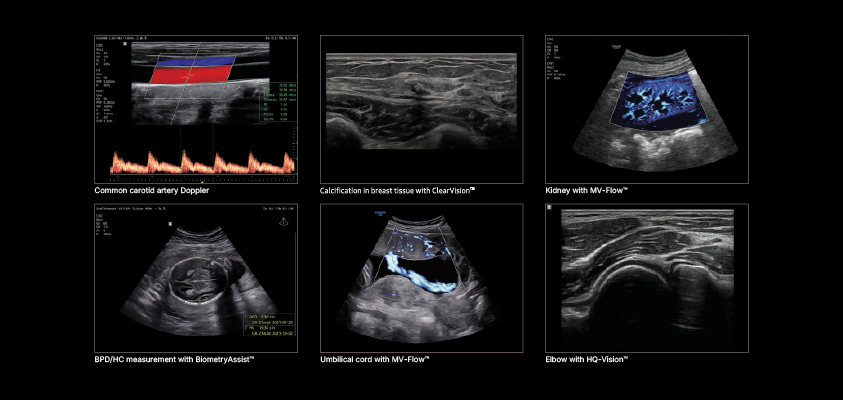

Structural anomalies (craniofacial malformations, limb defects, neural tube defects)

Congenital heart disease and other internal organ abnormalities

Fetal growth patterns and development milestones

Placental and amniotic fluid assessment